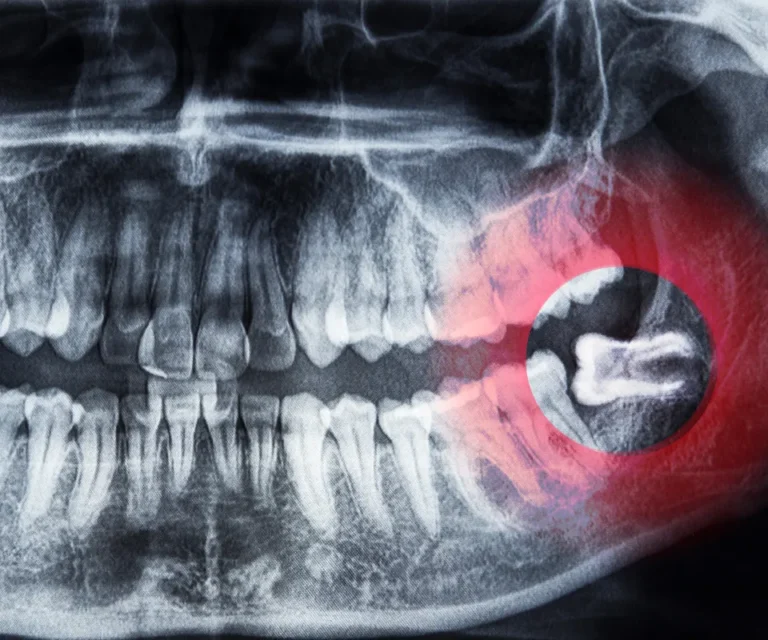

Wisdom Tooth Infection Emergencies

Wisdom teeth are especially prone to infection due to their position in the back of your mouth, making them harder to clean. Common signs of a wisdom tooth infection include:

Our emergency dentists in Little Rock can assess whether you need antibiotics, drainage, or immediate extraction to eliminate infection and pain.